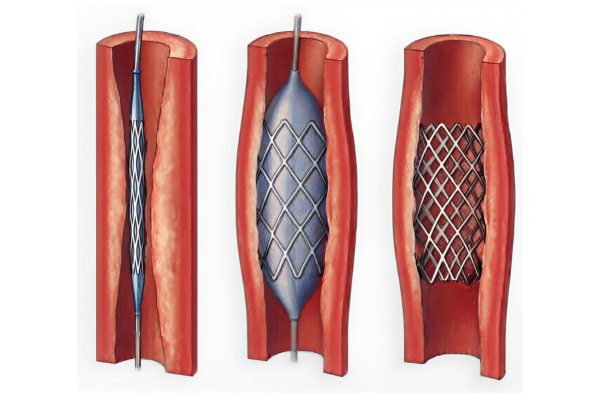

SMA narrowing reduces blood supply to the intestines, causing severe abdominal pain after meals and weight loss. This condition may progress to bowel ischemia if untreated.

SMA stenting opens the narrowed artery, restores intestinal blood flow, relieves pain, and prevents serious bowel damage through a minimally invasive procedure.